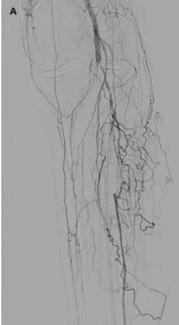

Infrapopliteal arterial disease results from 2 major etiologies: medial calcification and intimal atheromatous plaque. Lesion calcification constitutes one of the most widely encountered risk factors for percutaneous transluminal angioplasty...